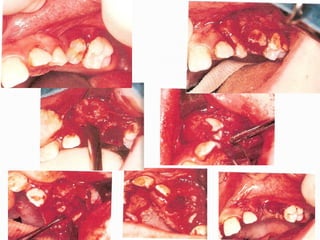

 Flap design

Flap should:-

1. be muco-periosteol.

2. Be cut 90º to bone.

3. Have a good blood supply.

4. Avoid damage to imp. Structures

5. Allow atraumatic reflection.

6. Provide adequate access and visibility.

7. Permit re-apposition of the wound margins over

sound bone.

Flap for buccaly placed teeth –

2 designs –

Ist Design-

Gingival margin as the horizontal component and a

vertical relief incision into the depth of the buccal

sulcus

2nd Design –

Semilunar incision, at least 5 mm of attached

gingiva should be maintained at the narrowest

point to ensure a good blood supply to marginal

gingiva.

Flap for palatally/lingually placed teeth –

Palatally positioned teeth are best removed via an

incision that follows the palatal gingival margin.

Such an incision maintain the integrity of greater

palatine nerve & vessels.

In the lower jaw adequate access to the lingual side

is obtained by raising the lingual gingiva &

reflected mucosa via an incision run around the

lingual gingival margin

 Bone Removal

this may be carried out using a hand piece and bur

or by the use of chisels.

 Tooth Removal

once sufficient bone has been removed to allow

identification of the tooth to be extracted &

exposure of the greatest diameter of its crown, the

tooth should be elevated.

 Suturing